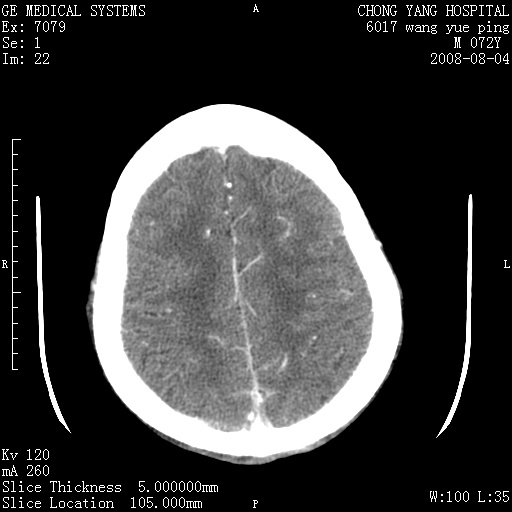

标题: CT14987:M72Y,头痛头昏,BP220/110. [打印本页]

标题: CT14987:M72Y,头痛头昏,BP220/110.

1)考虑左侧小脑脑梗塞。2)脑白质病。3)脑萎缩。4)双侧鼻腔新生物(息肉?)并阻塞性副鼻窦炎。

1.左侧小脑大面积梗塞;2.左侧基底节区腔梗;3.白质疏松;4.脑萎缩;5.慢性副鼻窦炎

小脑左侧病灶呈扇形分布,增强后未见明显瘤体样节结影,病变区未见强化。

支持:左侧小脑脑梗塞梗塞表现

另:脑白质病。脑萎缩。双侧鼻腔新生物(息肉?)并阻塞性副鼻窦炎。

1)考虑左侧小脑脑梗塞,建议治疗后复查除外其他,左基底节区腔隙性脑梗塞2)脑白质变性3)脑萎缩。4)双侧鼻腔新生物(息肉?)并阻塞性副鼻窦炎。